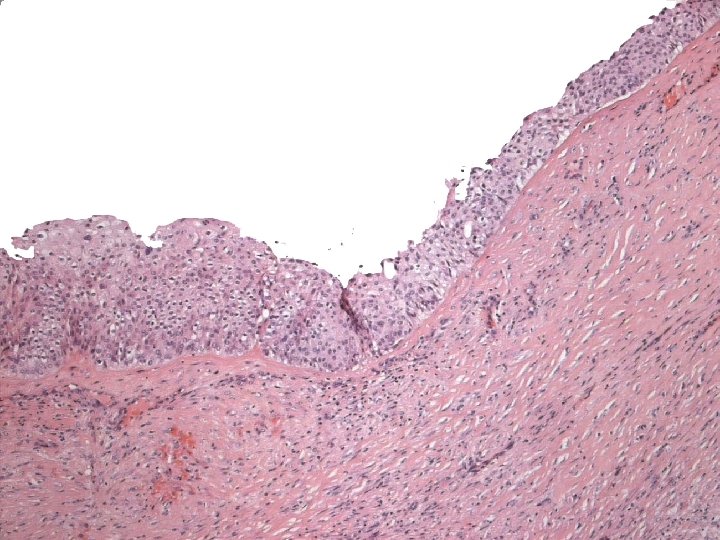

Micro The strongest evidence of a primary SCC of breast is presence of in-situ squamous carcinoma in duct or cyst lining.

Primary Squamous cell carcinoma A breast carcinoma entirely composed of metaplastic squamous cells that may be keratinising, non-keratinising or spindled; Exclude extension from skin and metastases. (WHO. 2003) Characterised by origin from squamous metaplasia in cyst, duct or both.

Micro n Similar to SCC at other sites n Cytoplasmic clearing in some